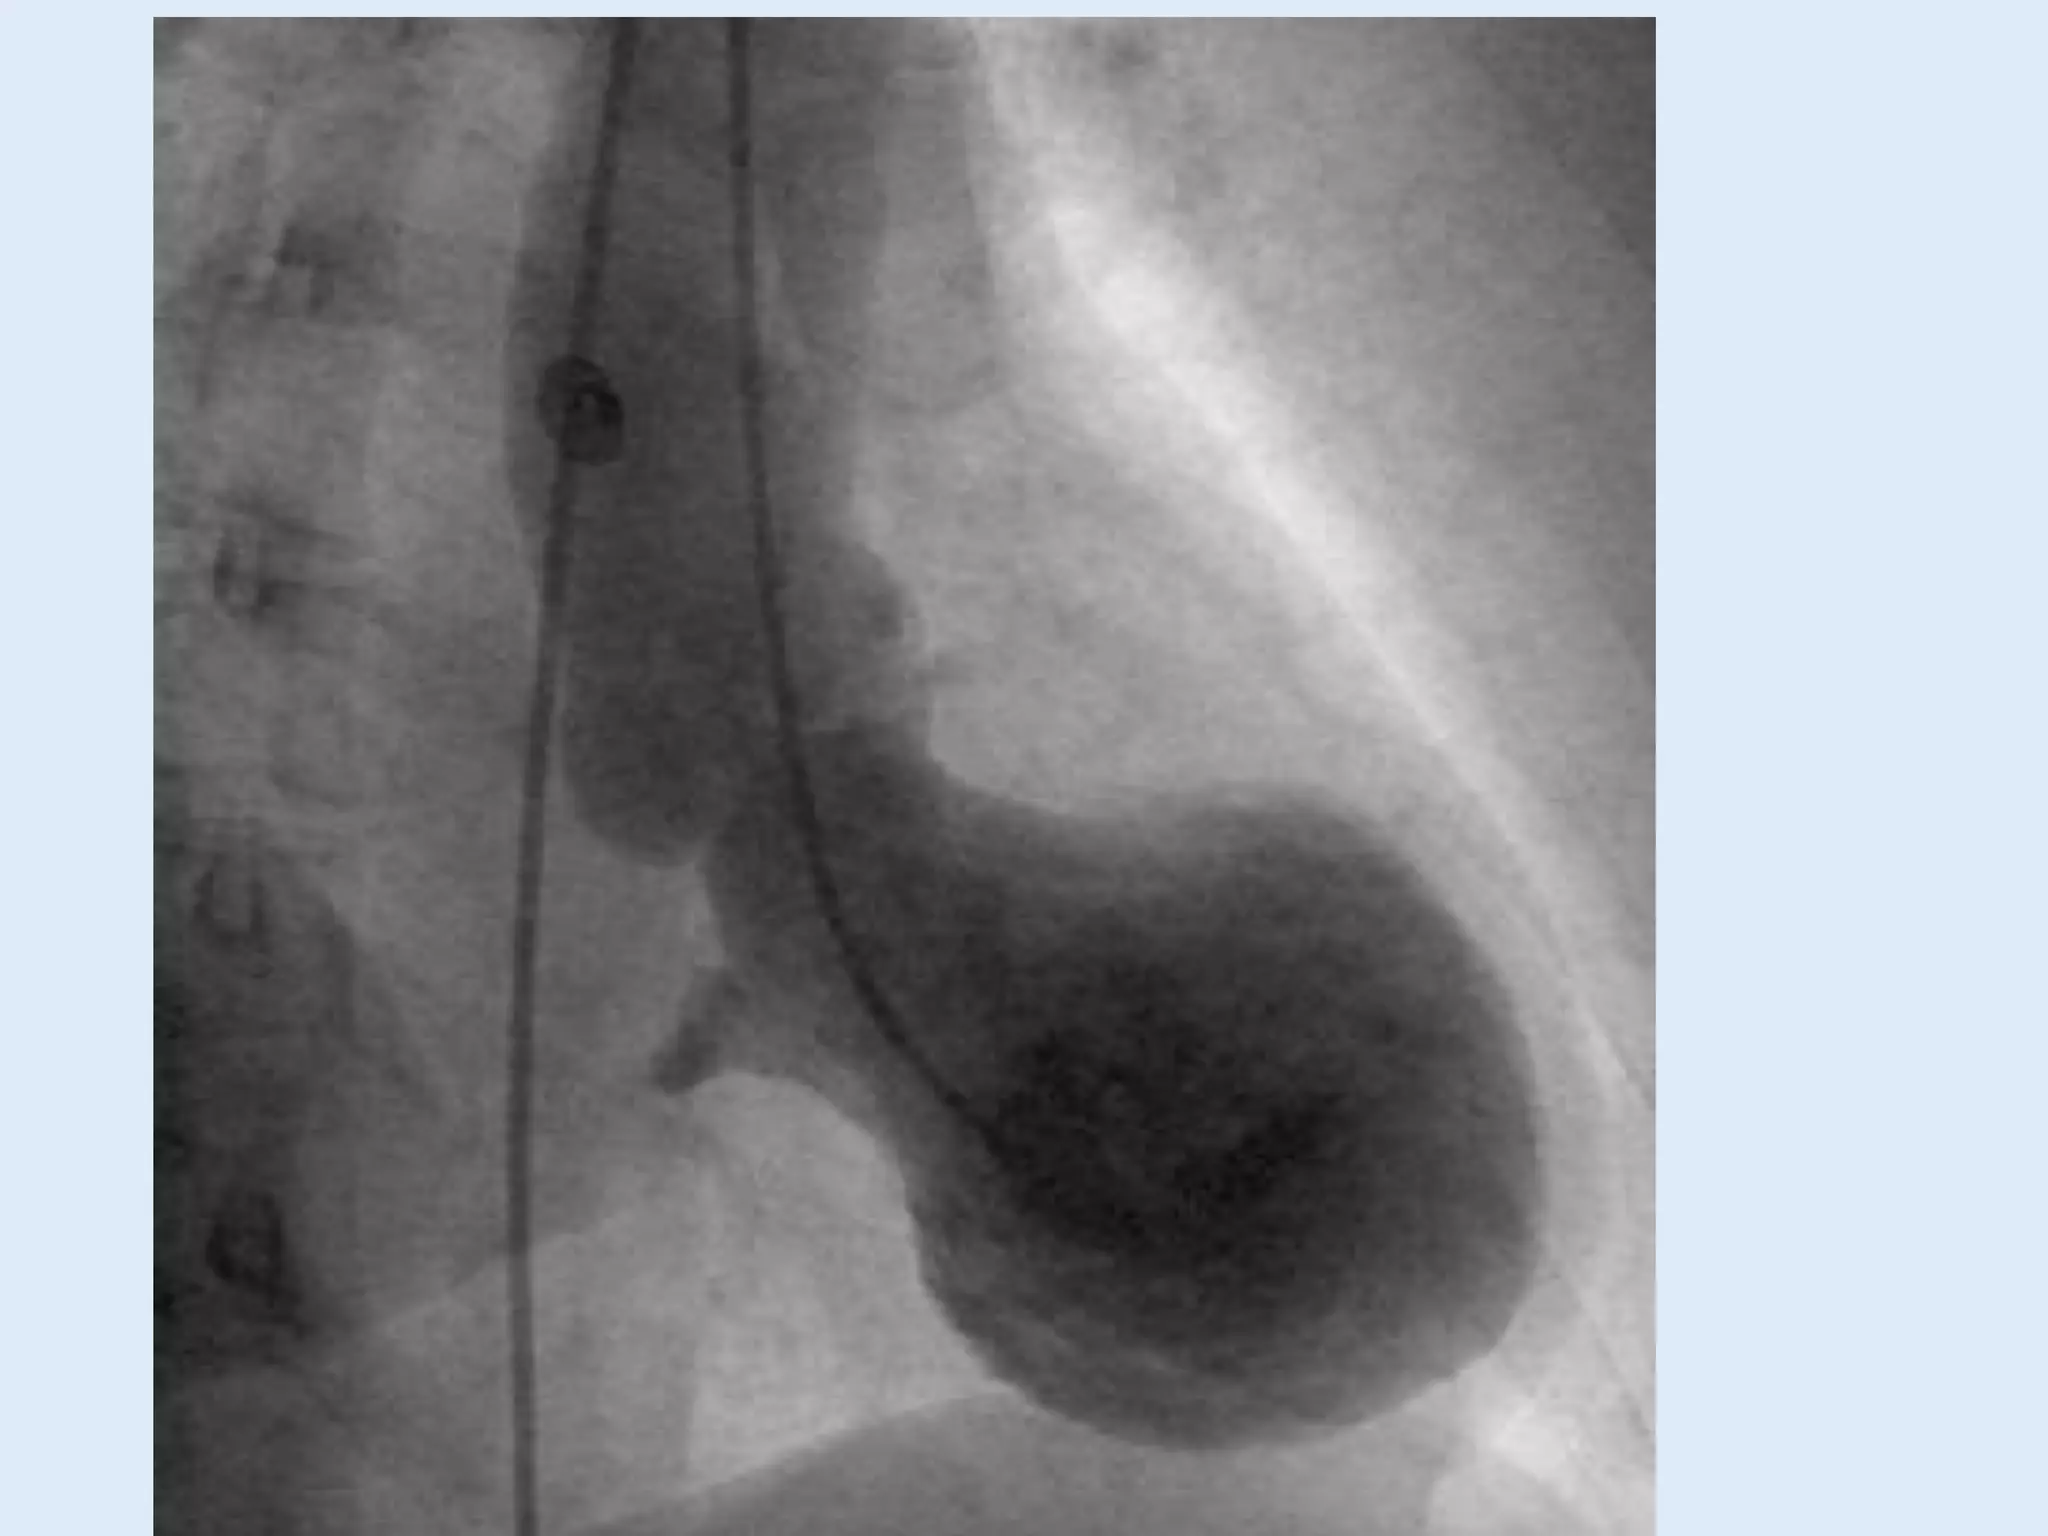

This document discusses right heart catheterization and the interpretation of pressure wave tracings from such a procedure. It notes that in a normal patient, right atrial and right ventricular pressure tracings will show smooth waves ranging and overshooting the right ventricular pressure. The tracing clearly shows the a wave of atrial contraction and the c wave of ventricular filling. It concludes by thanking the reader.